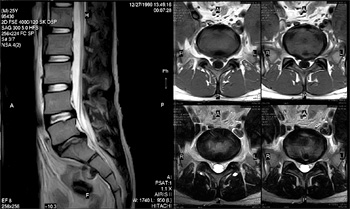

■ 神経根造影・ブロック

腰の神経の枝は左右に5ー6対あります。これを神経根といいます(図1)。椎間板ヘルニア等で臀部から足に痛みがある場合、多くはそのうちの1本または2本が圧迫されることが原因となっています。神経根造影は神経根に直接針を刺して、刺した神経根が現在の下肢の痛みの原因となっているかどうかを確定する検査です。また同時に痛み止めの薬と神経根の腫れ抑える薬(ステロイド剤)混ぜたものを直接神経に注入します。この注射でしばらくの間(数時間〜人によっては数週間)足の痛みがおさまることがあります。これが神経根ブロックです。